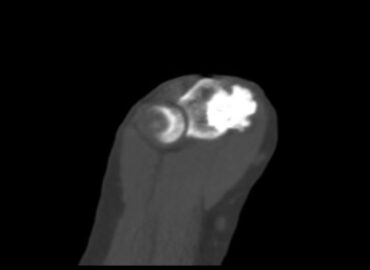

Paciente de sexo femenino de 37 años de edad, la cual refiere dolor en codo.